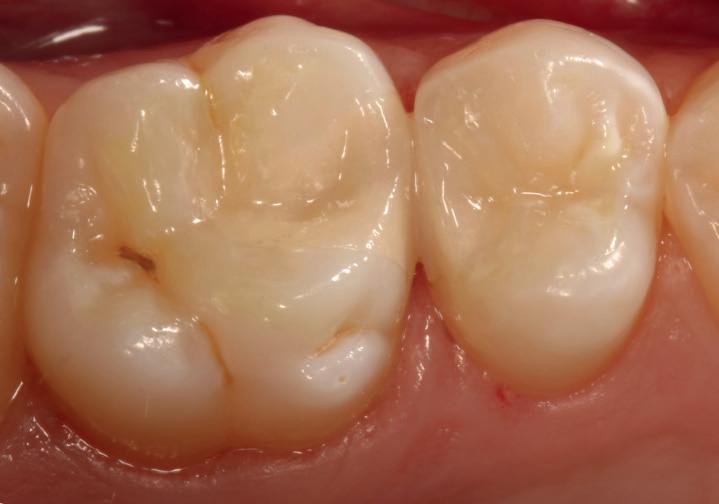

Case 2: Posterior tooth restoration with composite

Restorations with Beautifil II LS, Beautifil Flow Plus X and OneGloss by Erik-Jan Muts, M.Sc., Netherlands